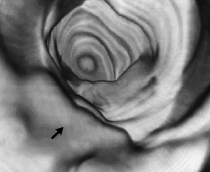

Comparaison entre l'image virtuelle et la réalité

3) Pour la visualisation et la reconstruction des images, les données acquises sont transférées sur une console de travail équipée de logiciels où elles sont analysées en coupes axiales 2D, en coupes multiplanaires et en 3D, avec une vision endoluminale. Le rendu volumique endoluminal fournit des images de meilleure qualité que le rendu surfacique. Il est possible de coupler les densités optiques avec une coloration jaune-rouge de la muqueuse virtuelle. La totalité des images obtenues sont revues coupe par coupe, avec un mode "Ciné-loop".